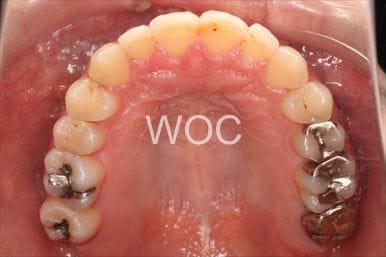

治療前1

治療前2

治療前3

治療前4

治療前5

- 年齢:20歳女性

- 主訴:出っ歯が気になる

- 基本矯正料金:120万円

- 治療期間:1年7ヶ月

- 抜歯部位:上顎両側第一小臼歯